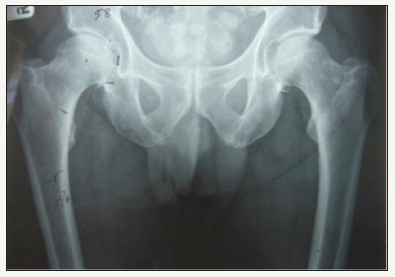

A 64 year old male underwent right total hip arthroplasty for osteoarthritis (Figure 1). A 58mm Pinnacle sector 2 acetabular cup with a neutral Marathon polyethylene liner (28mm ID x 58mm OD) was mated via a 28mm+5 high offset stainless steel Articul/Eze femoral head (12/14 cone) to an uncemented No 14 Corail stem. Post-op recovery was uneventful. Post-op X-Rays showed 37° of inclination of the cup (Figure 2).

figure 1: AP Pelvis showing right hip osteoarthritis.